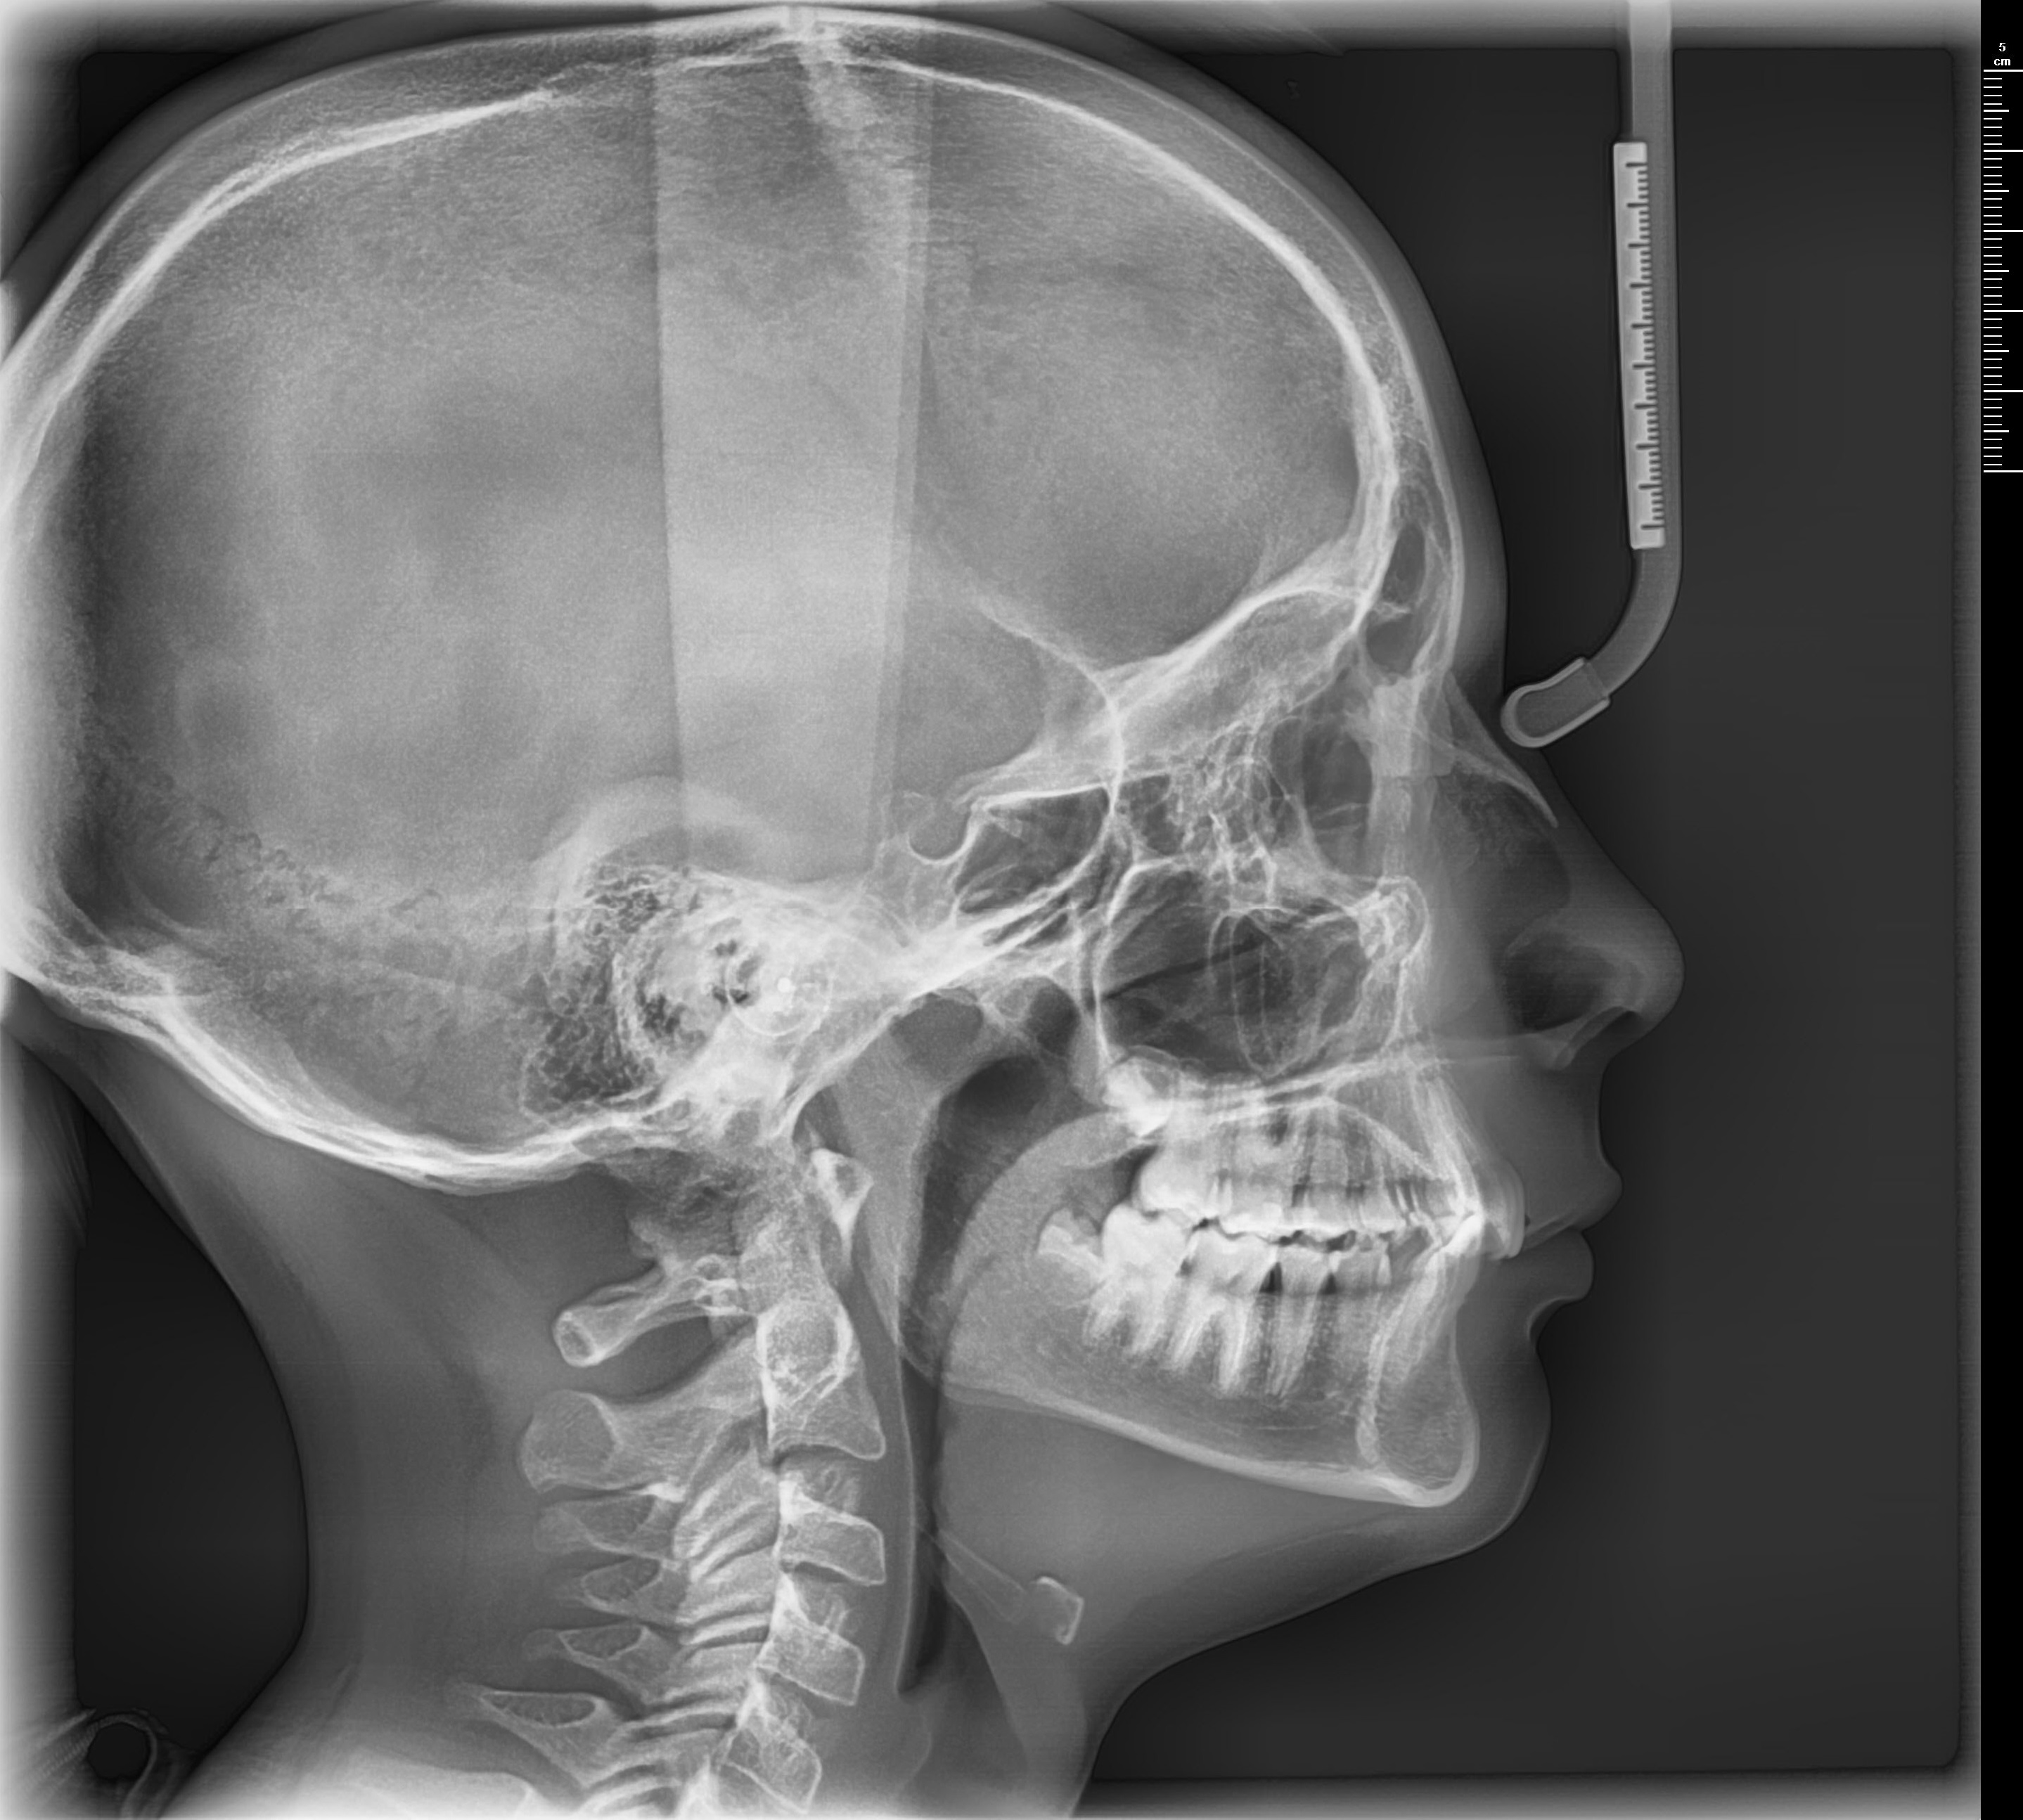

Tomógrafo 3D Dental con Ortopantomógrafo y Cefalostato.

- CBCT, Cone Beam Computer Tomography. Imágenes en 3D de 18 x 24 cm.

- FOV hasta 24 x 15 cm (Double Scan). Sensor 18 x 15 cm.

- Escaneo de modelos 3D.